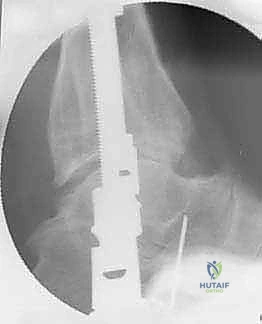

الخطوة الثانية: تركيب الإطار الخارجي (Ilizarov Frame)

هذه هي المرحلة الهندسية الدقيقة. يتم تركيب حلقتين معدنيتين حول عظمة الساق (Tibia) وحلقة ثالثة حول القدم (تثبت في عظمة العقب Talus وعظام مشط القدم).

الخطوة الثالثة: إدخال الأسلاك والمسامير (Wire and Pin Placement)

يتم تمرير أسلاك معدنية رفيعة جداً (Kirschner wires) ومسامير نصفية (Half-pins) عبر العظام لتثبيت الحلقات. يعتمد الأستاذ الدكتور محمد هطيف على معرفته التشريحية العميقة واستخدام جهاز الأشعة المرئي (C-arm) لضمان مرور هذه الأسلاك في "الممرات الآمنة" (Safe corridors) بعيداً عن الشرايين والأعصاب الحيوية.

الخطوة الرابعة: تركيب المفاصل الصناعية (Hinges)

هنا يكمن السر الأكبر للنجاح. يتم توصيل حلقة الساق بحلقة القدم باستخدام مفاصل معدنية قابلة للحركة (Hinges). يجب أن يتم وضع محور هذه المفاصل المعدنية ليتطابق تماماً مع المحور التشريحي الطبيعي لدوران مفصل الكاحل (Center of Rotation of the Talus). هذه الدقة تضمن إمكانية تحريك الكاحل أثناء فترة العلاج دون إحداث ضغط غير متساوٍ على الغضروف.

الخطوة الخامسة: تطبيق التشتيت (Distraction)

أثناء العملية، يقوم الدكتور هطيف بإبعاد حلقة الساق عن حلقة القدم تدريجياً وببطء باستخدام قضبان ملولبة، حتى يصل إلى مسافة تشتيت تبلغ حوالي 5 إلى 6 ملليمترات. يتم التأكد من هذه المسافة عبر الأشعة السينية داخل غرفة العمليات.